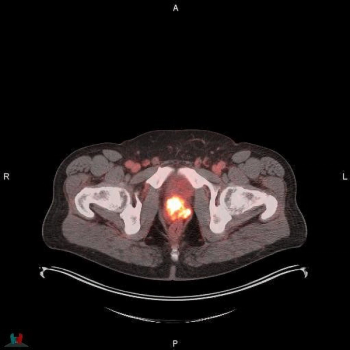

For patients initially diagnosed with non-metastatic, castration-resistant prostate cancer, pelvic lymph node involvement and five or more polymetastases detected with prostate-specific membrane antigen (PSMA)/ positron emission tomography (PET) are significantly associated with lower overall survival rates, according to recently presented research at the American Society of Clinical Oncology (ASCO) conference.

Reportedly the first FDA-approved PSMA PET agent with proprietary radiohybrid technology, POSLUMA can be utilized for positron emission tomography (PET) scans of prostate-specific membrane antigen (PSMA) positive lesions in men with prostate cancer and suspected metastasis, and those with suspected prostate cancer recurrence based on an elevated serum prostate-specific antigen (PSA) level.